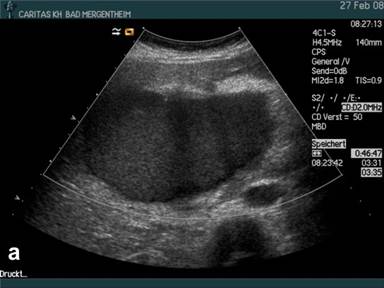

Vascularisation of a mass lesions or cystic lesion with peripherally located nodules with or without septae (shown by B-mode) were analysed and afterwards assessed by CEUS analysing the contrast enhancement; it was differentiated if a macrovessel was transversing the nodule at the edge of a septum as a sign of preformed vessel transversing the pseudocyst (or necrosis) or microvascularity could be shown within the solid nodule as a sign of neoangiogenesis of neoplasia. Results were compared with histology assuming that pseudocysts (with the exception of individual macrovessels transversing the pseudocyst) in contrast to microvascularised neoplasia do not show contrast enhancement (Figure 1). In addition malignant lesions were assumed to be hypovascular in comparison to the surrounding pancreatic parenchyma according to the European Federation of Societies for Ultrasound in Medicine and Biology (EFSUMB) guidelines [1] and recently published studies [3, 4].

Figure 1. B-mode imaging (a.) and contrast enhanced ultrasound (CEUS) (b.) in a patient with histologically proven pseudocyst of the pancreas. Small peripherally nodular structures are delineated (arrow) analysing the arterial phase (b.) indicating neoplasia. Surgery and consecutive histology revealed pseudocyst and no neoplasia. |

Using conventional B-mode mostly peripherally located solid nodules (with or without septae formation) were displayed in 36/64 (56.3%) patients implying neoplastic disease. The results are shown in Table 2. In 2/36 (5%) of these patients with nodules at the edge of the cyst and the final diagnosis of pseudocyst contrast enhancement was found in the peripherally located solid nodules (Figure 1) which was the reason for the 2 false positive findings using CEUS in histologically/cytologically proven pseudocysts. The pseudocyst transversing arterial macrovessels could only be identified using CEUS and conventional ultrasound in combination in 13/35 (37.1%) patients.